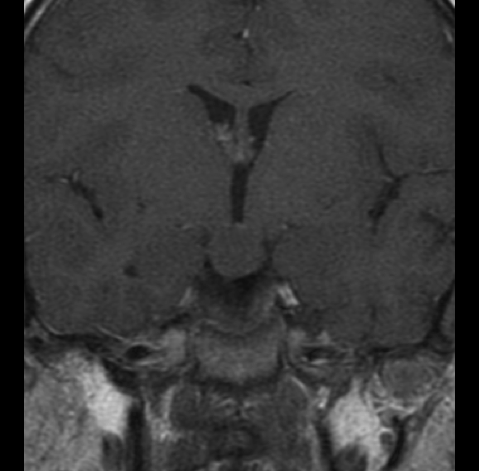

Niña de 7 años. Se solicita RM hipofisaria por pubertad precoz.

T1 + Gadolinio